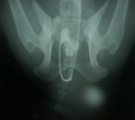

初診時逆行性尿路造影DV像。骨盤外の膀胱に造影剤が貯留していた。 同lateral像。前立腺直前より造影剤が逆流し、前立腺が造影された。 術中所見。会陰ヘルニア整復術。鉗子の先は反転した内閉鎖筋弁。 同。結腸膀胱固定術。下行結腸を左腹壁に固定。膀胱は指で保持。

経過:初診時、直腸温計測できず、心拍数:68/分 呼吸数:28/分。左会陰部が波動感ある著しい腫大を呈していた。試験穿刺を行ったところ尿が360ml採取された。鎮静下にて、尿道カテーテルを介した逆行性尿路造影で前立腺直前に強い抵抗あり尿道内に造影剤が逆流してきた。DV像にてわずかに骨盤外の膀胱に造影剤が貯留しており、lateral像では前立腺管に造影剤が流入し肥大した前立腺が造影された。前立腺直前の尿道が後方に屈曲しヘルニア嚢内に膀胱が嵌頓していることが分かった。排便障害は、前立腺肥大にも原因があると思われた。血液生化学検査でいまだ尿毒症に至っていないことを確認した。ただちに、外科的に左側会陰ヘルニアの整復術、膀胱や結腸嵌頓防止のための腹腔内結腸膀胱固定術、前立腺肥大治療のための去勢術を行った。まず、会陰部切皮前に再度経皮的穿刺し採尿したあと膀胱をヘルニア孔の腹腔側に向け指でできる限り押し入れながら導尿カテーテルを進め、膀胱を環納した。ヘルニア整復は、内閉鎖筋腱を切断し弁状に反転したもの、外肛門括約筋、尾骨筋のそれぞれをマットレス縫合であわせ閉鎖した。結腸膀胱固定術は開腹下にまず下行結腸を左腹壁に3-0Dexonにて4糸の結節縫合にて固定し、その後膀胱の体部を結腸に2糸縫合し反転しないようにした。閉腹後、去勢手術を行った。術後翌日より食欲あり一般状態は改善した。術後8日で痛みなく排便可能となった。飼い主によると、この犬はとても神経質でケージに入ると鳴きわめき、人に咬みつく事があるかもしれないということだったが、手術による整復後、性格は温厚になり、忠実に言うことをきくようになった。術後10日で抜糸完了し退院となった。退院3週間後オーナーより連絡があった。快食快便となり、以前は好物をやっと食べるだけであったが今は何でもすぐに食べ、性格が明るくなった。以前は物陰に隠れたり、人目を盗んで脱走したりするような陰気な性格であったが、退院後そのようなことが全くなくなったという。